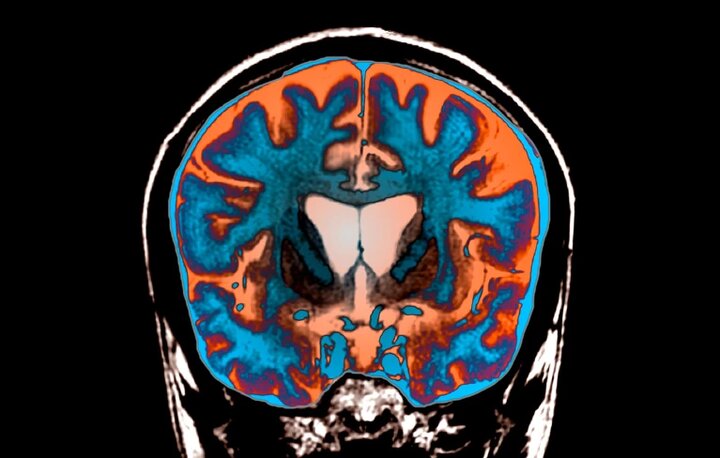

مطالعهای که در مجله Cell منتشر شده، بر روی نورونهای استریاتال، که اولین نورونهای آسیبدیده در هانتینگتون هستند، متمرکز شده است، محققان با بررسی مغز شش فرد مبتلا به هانتینگتون دریافتند که تعداد تکرارهای CAG در این نورونها به طور قابل توجهی افزایش یافته است. برخی نورونها حتی بیش از ۱۵۰ تکرار CAG داشتند، این افزایش ناشی از خطا در فرآیند ترمیم DNA است که هنگام رونویسی RNA رخ میدهد و موجب ایجاد حلقههایی در DNA میشود. پروتئینهای ترمیمکننده DNA سعی در رفع این خطاها دارند، اما اغلب موجب افزایش تعداد تکرارها میشوند.

نورونهایی که تعداد تکرارهای CAG در آنها از حد معینی فراتر میرود، دچار تغییرات شدیدی میشوند، ابتدا ژنهایی که هویت نورونها را مشخص میکنند، غیرفعال میشوند و سپس ژنهای مرتبط با مرگ سلولی فعال میشوند. این فرایند در نهایت منجر به مرگ نورونها میشود، این یافتهها نشان میدهند که پروتئینهای ترمیم DNA میتوانند اهدافی امیدوارکننده برای درمان هانتینگتون و سایر بیماریهای مشابه باشند، مهار این پروتئینها ممکن است شروع بیماری را به تأخیر انداخته یا پیشرفت آن را کند کند.